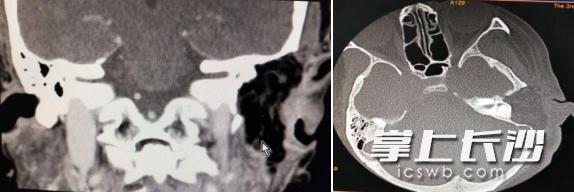

专家为患者制定了详细的手术治疗方案。术中发现,患者不仅耳道前壁有骨质破坏,外耳道底壁,面神经垂直段骨管均存在骨质破坏,面神经垂直段甚至被肿瘤包裹达270度,手术难度提升,稍有不慎,有可能面神经受损,患者可能面临面瘫的风险。刘国辉手术团队小心、细致地操作,慢慢地将肿瘤一点点清理干净,手术历时3个多小时,终于顺利进行。术后检查患者无面瘫,恢复良好,今日已出院。

术后检查片